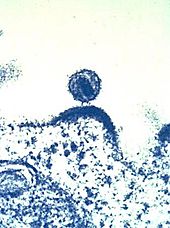

HI-Viren sammeln sich vor dem Verlassen der Immunzelle an der Membran.

HI-Virus, das sich aus einer Immunzelle herauslöst.